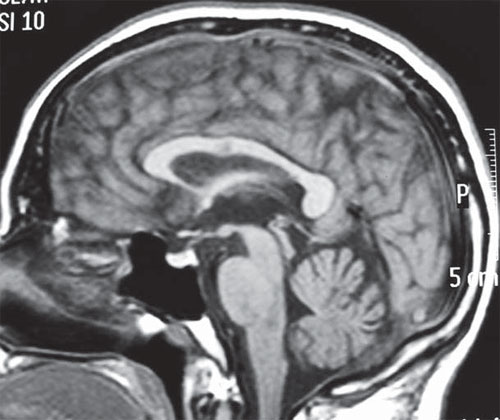

Fenitoína: los niveles séricos elevados pueden producir atrofia cerebelosa